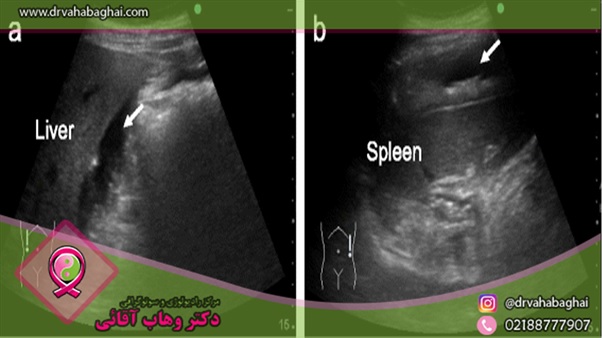

تمامی اندامی که در ناحیه شکم قرار دارند با استفاده از سونوگرافی شکمی قابل بررسی هستند. برخی از مهم‌ترین تصویربرداری‌های بافتی از داخل شکم که به کمک دستگاه اولتراسوند انجام می‌گیرد عبارت‌اند از:

•          سونوگرافی طحال

•          سونوگرافی کبد

به عنوان یک کاربرد مهم سونوگرافی شکمی لگنی به یک مثال اشاره می‌کنیم. فرض کنید فردی با سنی حدود 65 تا 75 سال به مصرف سیگار اعتیاد دارد و یا داشته و در حال حاضر دچار درد در ناحیه شکم است. پزشک در چنین شرایطی معمولا برای بررسی آنوریسم آئورت شکمی (Abdominal Aortic Aneurysm)، انجام سونوگرافی شکمی را تجویز می‌کند.

•         تغییرات اندازه در اندام‌های مهم نظیر طحال، کلیه و کبد